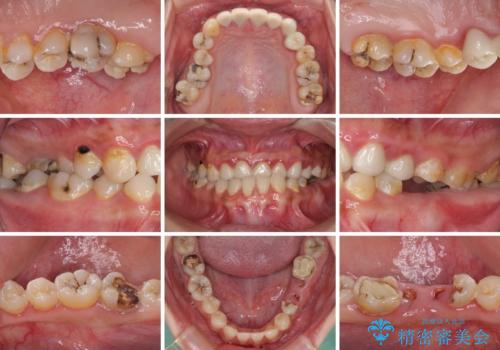

むし歯だらけの奥歯 セラミッククラウンによるむし歯治療

- 奥歯のむし歯を気にして来院された患者様です。

痛みのある歯が多く、根管治療が必要と診断されました。

左下の歯は、クラウンを装着するために必要な高さが足りないため、歯冠長を延長するための外科処置を行うこととしました。

根管治療や歯周外科処置後にフルジルコニアクラウンにて補綴治療することとしました。

自身の口腔内への意識が高くなく、汚れが非常に多い方でした。